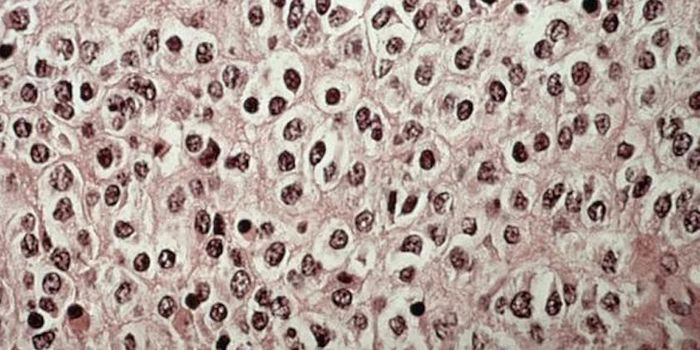

JUN 01, 2016CancerInvasive cervical cancer will be diagnosed in nearly 13,000 American women this year. Although routine Pap screening has ...